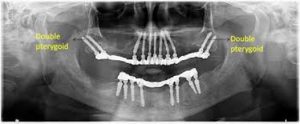

ایمپلنت های پتریگوئید Pterygoid در محل اتصال استخوان فک بالا قرار می گیرند و معمولاً ۱۲ تا ۲۰ میلی متر طول دارند. آنها اغلب در ترکیب با ایمپلنت های زیگوماتیک برای ایجاد ثبات بیشتر استفاده می شوند. ایمپلنت های زیگوماتیک که در استخوان گونه قرار می گیرند، را می توان با میله های پرچم مقایسه کرد. درست مانند میله پرچم که برای ثابت ماندن در بادهای شدید به تکیه گاه نیاز دارد، ایمپلنت های زیگوماتیک برای ثبات بهینه به اتصال به ایمپلنت های دیگر نیاز دارند. بدون این اتصال، نوک ایمپلنت زیگوماتیک ممکن است حرکت جزئی داشته باشد.

در مواردی که بیماران استخوان محدودی در دسترس دارند، می توان از ایمپلنت های پتریگوئید استفاده کرد زیرا ممکن است نواحی مناسبی برای ایمپلنت های استخوانی سنتی وجود نداشته باشند. ایمپلنت های پتریگوئید در استخوان قشری متراکم موجود در ناحیه دندان عقل فک بالا، که به عنوان صفحه پتریگوئید شناخته می شود، تکیه داده می شوند. با اتصال ایمپلنت های پتریگوئید به ایمپلنت های زیگوماتیک، یک پایه بسیار پایدار ایجاد می شود که می تواند به طور مؤثر از پروتز ثابت پشتیبانی کند.